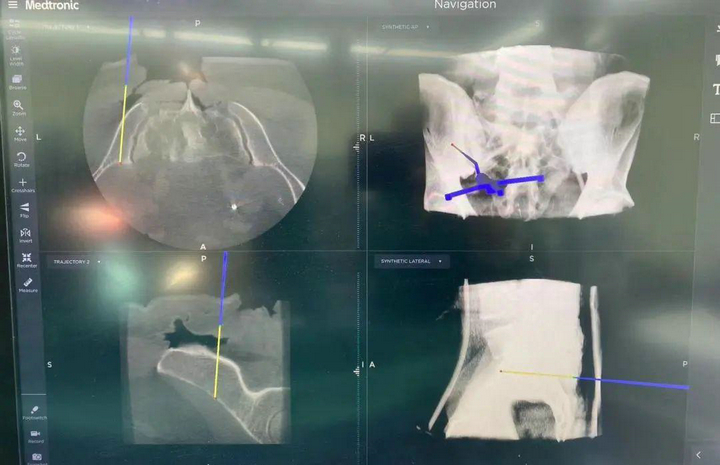

“O”型臂導(dǎo)航系統(tǒng)是一種先進(jìn)的骨科手術(shù)輔助設(shè)備,能精準(zhǔn)定位腫瘤。該系統(tǒng)由“O”型臂術(shù)中影像和手術(shù)導(dǎo)航系統(tǒng)組成,在骨科手術(shù)中發(fā)揮著重要作用,為手術(shù)醫(yī)生實(shí)時(shí)提供術(shù)中三維立體影像,使得手術(shù)醫(yī)生的視角更廣,幫助醫(yī)生避開周圍重要的血管和神經(jīng),精準(zhǔn)定位病變部位和范圍,確保了腫瘤的完整切除和正常骨質(zhì)的最大程度保留,大大提高了手術(shù)的安全性。

精準(zhǔn)切除腫瘤后,借助骨腫瘤科自主研發(fā)的3D打印組合式半側(cè)骶骨假體進(jìn)行重建。并在O臂導(dǎo)航系統(tǒng)的引導(dǎo)下,精確放置假體和螺釘,進(jìn)一步提升患者的重建效果。此外,該系統(tǒng)還可以縮短手術(shù)時(shí)間,加快患者的康復(fù)。